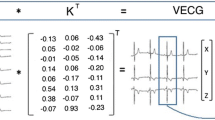

Phase analysis

Phase images were created using a first-order harmonic fit of the time–activity curve for each pixel, representing the timing of ventricular contraction relative to the R wave of the ECG.26,27 The phase angle defines the point in the time–activity curve where the Fourier function reaches its peak, representing the onset of contraction. An example of a phase and amplitude image with the associated time–activity curve and phase histogram for a patient with normal ventricular contraction is shown in Figure 1. The R–R duration is measured in seconds but can be converted to degrees, where 360° represents the length of one cardiac cycle. Any areas of dyssynchronous contraction will appear as delays in the phase images and phase histogram.

In-house software was used to calculate synchrony, entropy, ApEn, SampEn, and phase SD from the RNVG phase images both pre and post beta-blockade. To calculate synchrony, each pixel within the ROI was defined by a vector where the length was defined as the amplitude (maximum change in counts), and the direction was defined as the phase angle. Synchrony is then defined as the vector sum of the pixel values divided by the scalar sum. A ventricle with completely synchronous contraction would have a synchrony value of 1 and a completely asynchronous contraction would have a synchrony value of 0. Entropy, as derived from Shannon information theory,28 was used as a measure of randomness in the phase histogram.16 A higher value of entropy indicates a more random contraction.